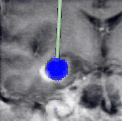

The intervention requires a precise placing of a catheter, an optical fiber tip or another surgical device within the tumor. The access to the tumor is chosen such that essential brain areas and blood-vessels are circumvented. Intraoperatively, the placement can be controlled by 2D images produced by the interventional MRI system during the intervention. The images have to be registered with the preoperative reference scene together with synthetic images of access path and surgical device to provide the surgeon with the necessary spatial and structural orientations.

For the laser-induced interstitial thermotherapy, the tumor tissue is coagulated by laser energy as a second step. The propagation of the coagulation process depends on various parameters (e.g., laser energy, absorption, blood perfusion) and has to be controlled whether the coagulation follows the anticipated pattern. Otherwise, the exposition time and dose have to be adapted. Temperature distribution can be controlled by images produced by the interventional MRI system during the intervention.

MR systems can also be used to measure the temperature within the brain during a laser-induced interstitial thermo therapy. As the coagulation process is difficult to predict due to irregularities in tissues and thermo convection, an interventional MR system can be used to control whether the therapy proceeds as planned or whether the plan has to be modified. This asks for a fusion of current MR images with respective images of the therapy planning.